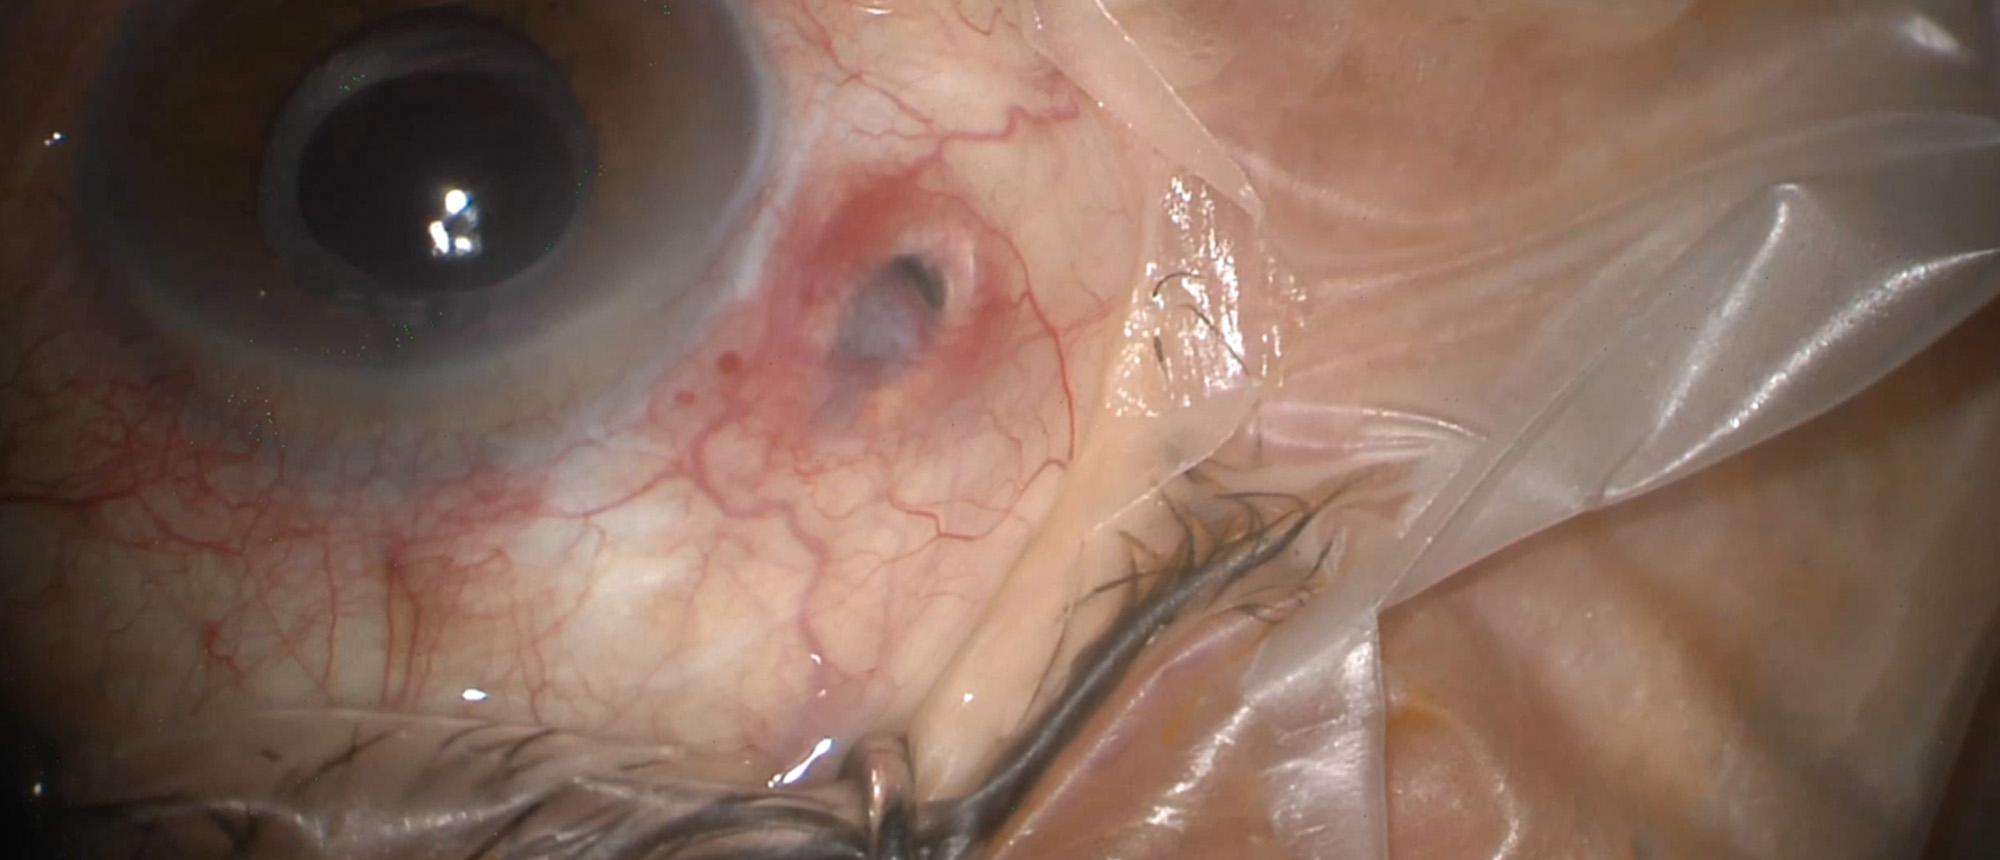

Specialty: Retina and Vitreous Diseases

Presenter(s): Da Meng, MD, PhD

Faculty Discussant(s): Thomas A. Albini, MD; Janet L. Davis, MD; Sander R. Dubovy, MD